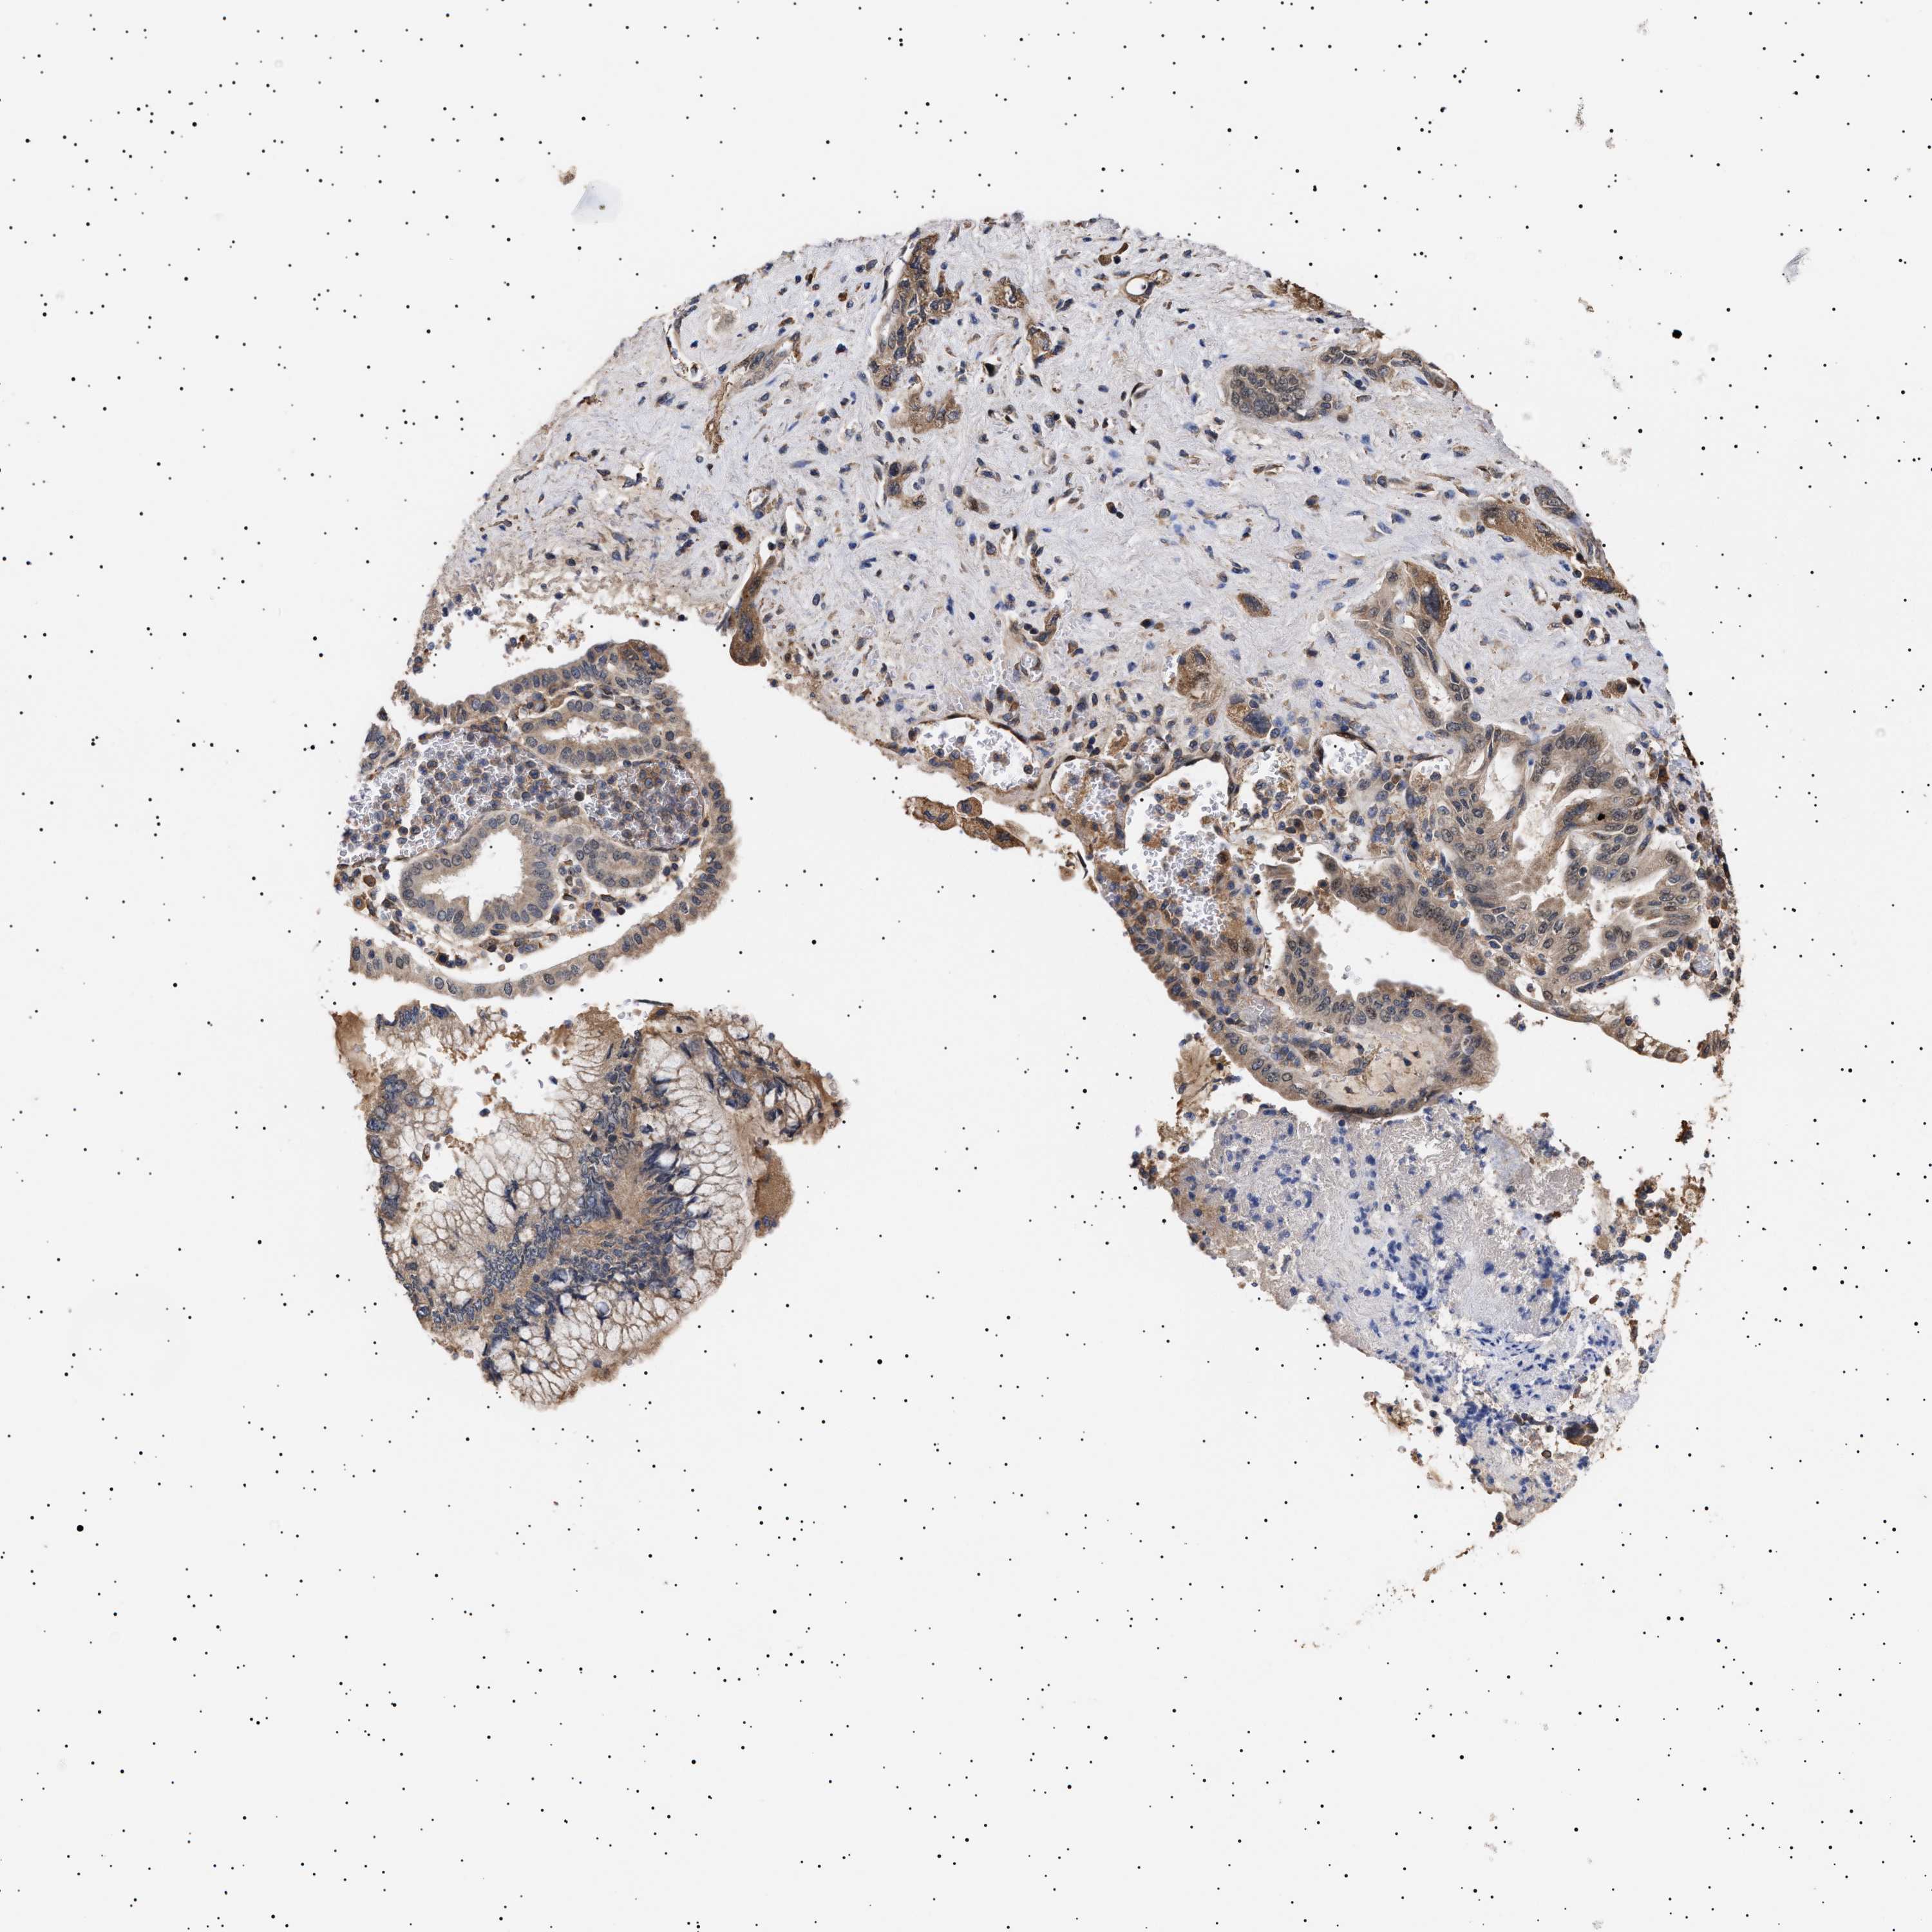

PANCREATIC CANCER - Protein expressioni

A mouse-over function shows sample information and annotation data. Click on an image to view it in a full screen mode. Samples can be filtered based on level of antibody staining by selecting one or several of the following categories: high, medium, low and not detected. The assay and annotation is described here.

Note that samples used for immunohistochemistry by the Human Protein Atlas do not correspond to samples in the TCGA dataset.

Antibody stainingi

Antibody staining in the annotated cell types in the current human tissue is reported as not detected, low, medium, or high, based on conventional immunohistochemistry profiling in selected tissues. This score is based on the combination of the staining intensity and fraction of stained cells.

Each image is clickable and will lead to virtual microscopy that enables deeper exploration of all samples and also displays staining intensity scores, fraction scores and subcellular localization as well as patient and tissue information for each sample.

Antibody HPA021237

Antibody HPA050448

Adenocarcinoma, NOS